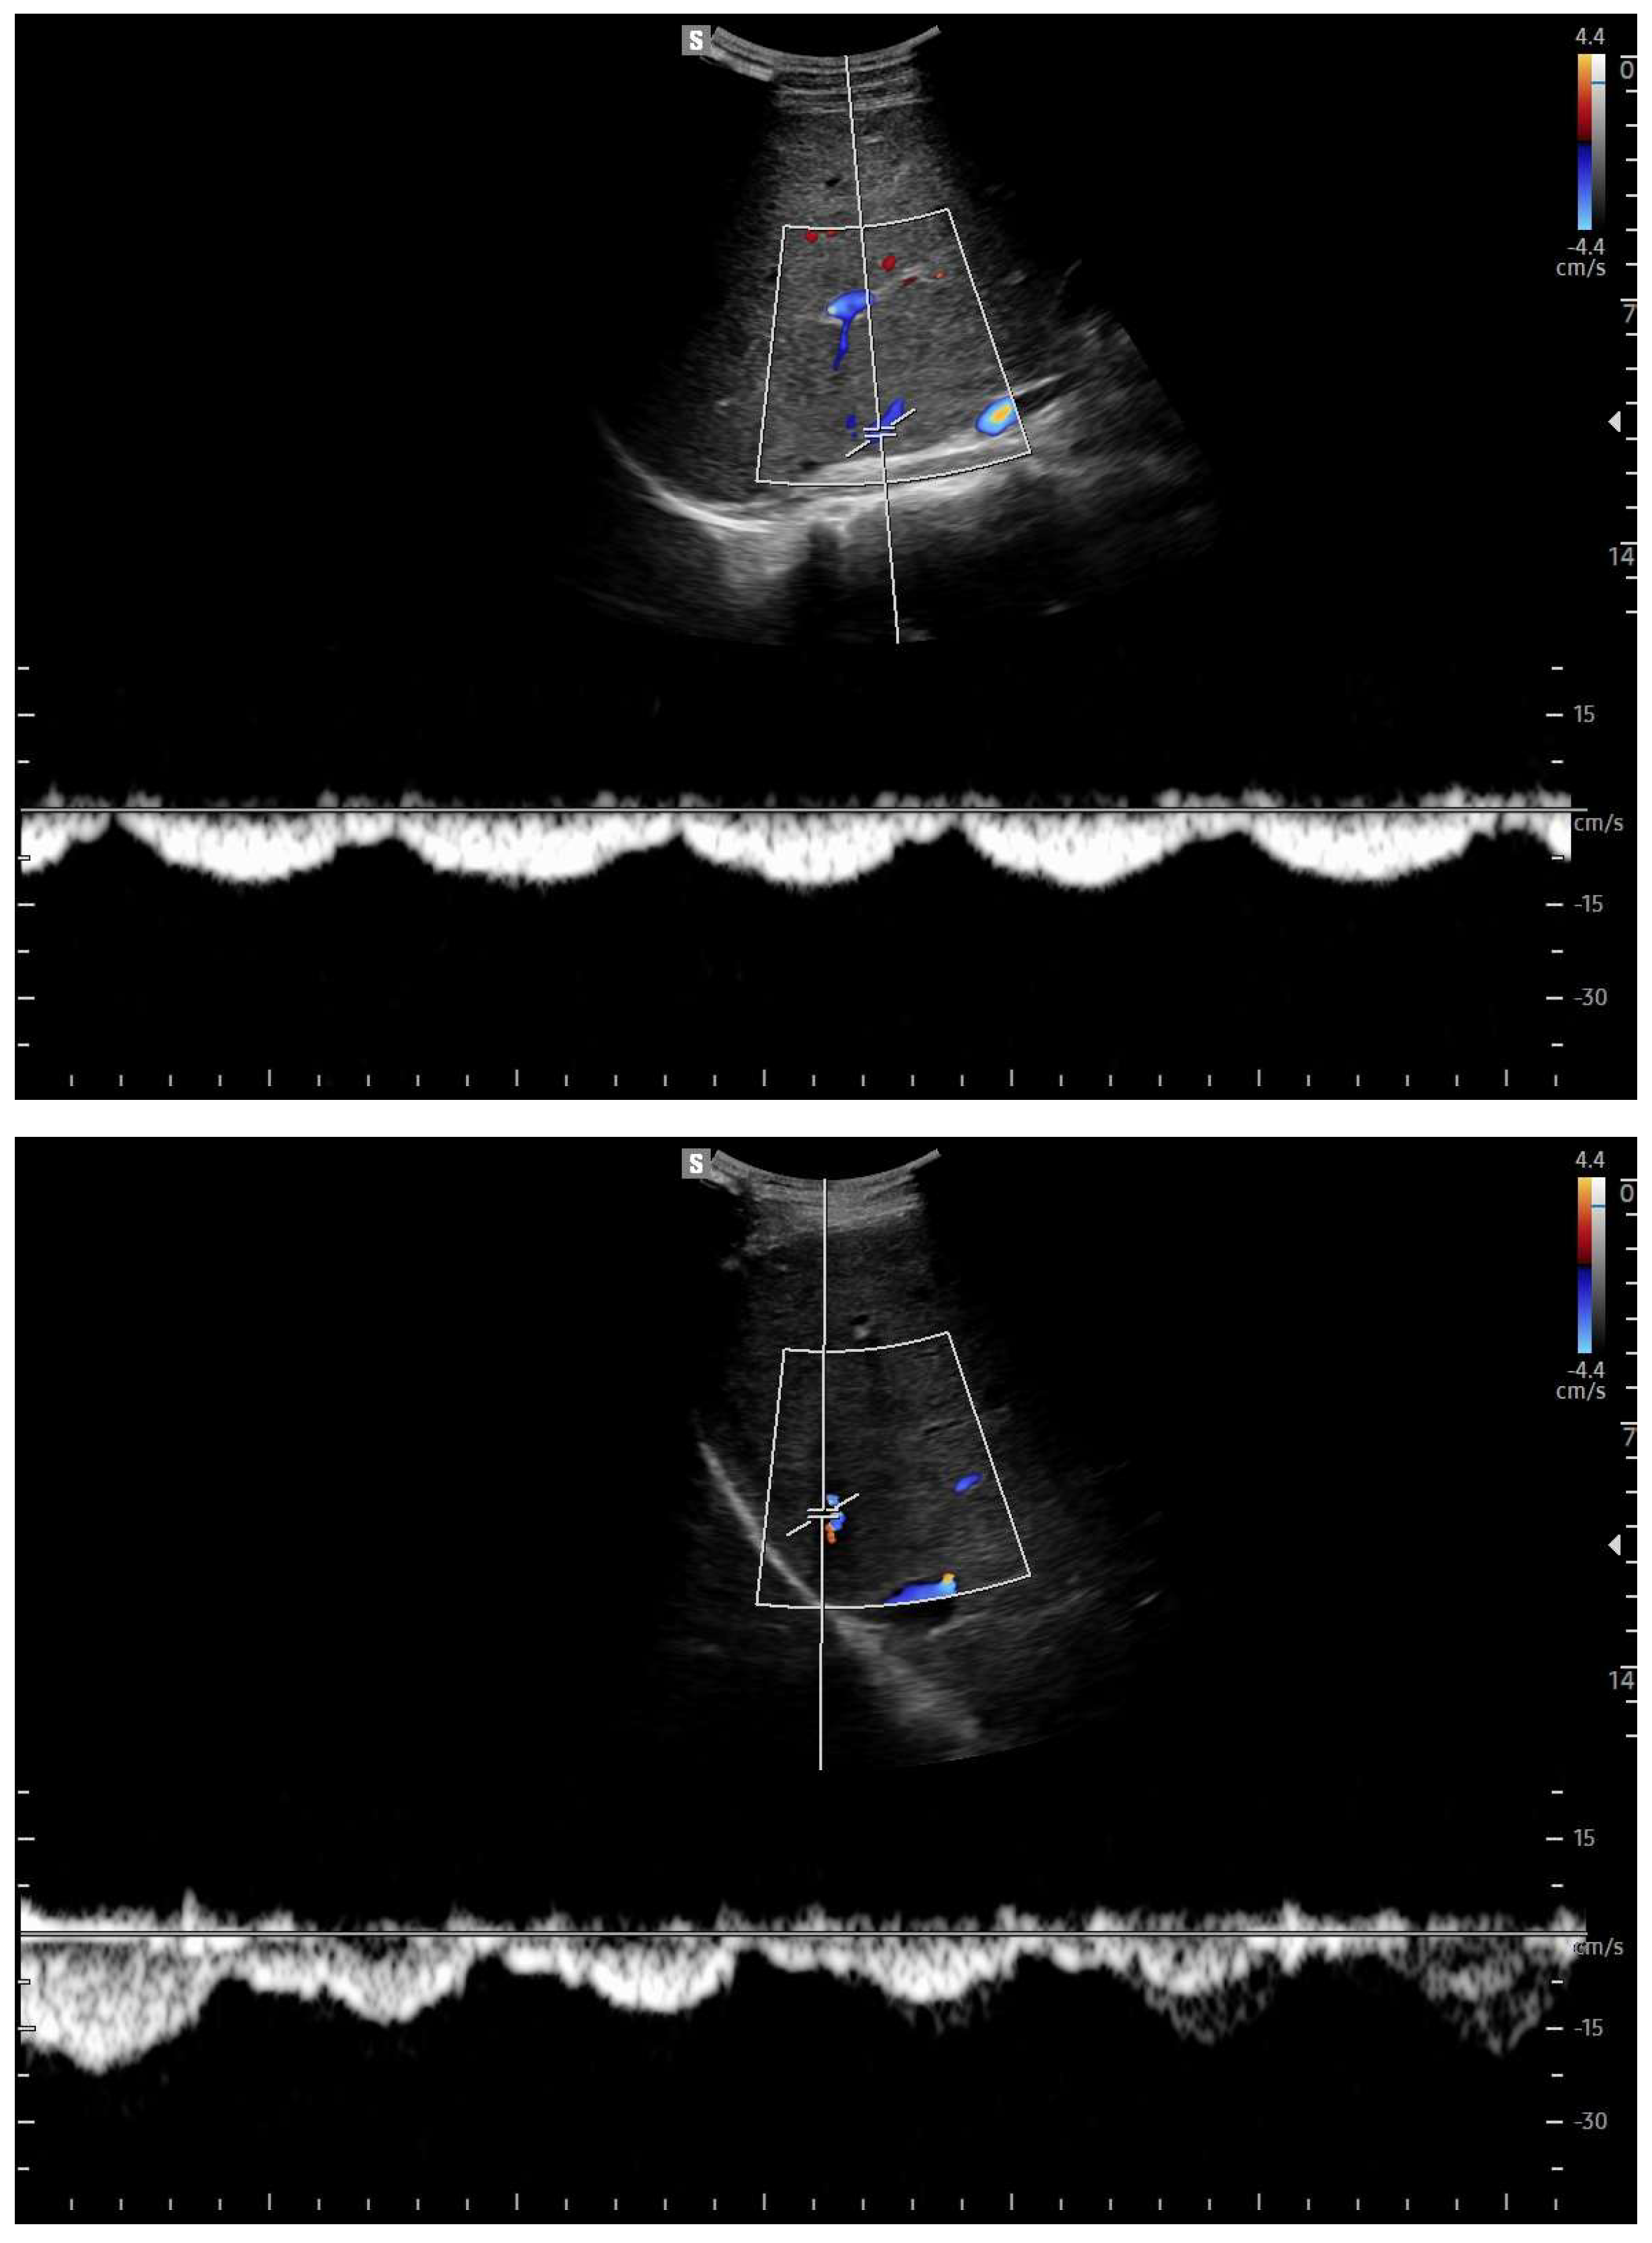

Doppler patterns in Fontan patients resemble those observed in chronic liver disease, including reduced portal flow velocity (mean flow velocity < 14 cm/s) [56]. The Fontan procedure inevitably alters hepatic venous waveforms on Doppler US (Figure 10, Figure 11, Figure 12 and Figure 13). Inverted portal flow has a specificity of 100% for diagnosing PHTN [57] (Figure 12). The hepatopetal phase pattern in the hepatic vein differs between patients with total cavo-pulmonary anastomosis (including both lateral tunnels and extracardiac conduits) and those with atrio–pulmonary connection [58,59,60]. In atrio–pulmonary connection, hepatopetal flow is preserved (Figure 10), reflecting the exclusion of atrial contribution to venous circulation, whereas in total cavo-pulmonary anastomosis, flow reversal (Figure 11) occurs only during early expiration. Similarly to congestive heart failure, hepatic veins and the IVC are dilated, with abnormally increased hepatic vein pulsatility, regardless of the anastomosis technique [54,61,62]. The loss of the normal three-phase Doppler pattern in hepatic veins is universal following bi-cavo-pulmonary surgery due to the absence of atrial contraction. The presence of a monophasic pattern indicates advanced liver injury [63].

Figure 10.

Doppler Ultrasound of the middle hepatic vein showing the loss of the normal three-phase pattern due to the absence of atrial contraction.

Figure 11.

Preserved hepatopetal portal flow in atrio–pulmonary connection.

Figure 12.

Inverted portal flow in cavo-pulmonary anastomosis.

Figure 13.

Changes in hepatic vascularization in a patient with FALD. The middle hepatic vein is patent, although irregular, within the context of the parenchymal nodularity.